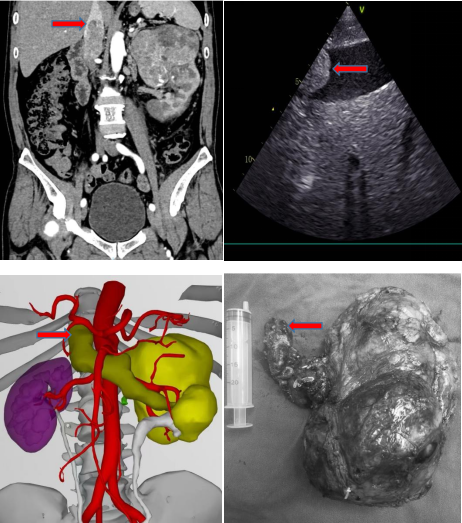

??患者王某,男,54岁,因“左腰部疼痛加重1月,无痛血尿1周”入院,术前贫血。完善相关检查后,腹部CT示左肾恶性肿瘤并出血,左肾静脉、下腔静脉及左侧腰静脉栓形成;上腹部MRI检查考虑左肾癌(最大径25cm)并II级下腔静脉瘤栓(越过第三肝门上方至第二肝门下缘),下腔静脉瘤栓最大截面约:6.2cm(cor)×2.3cm(aix)。

??红色箭头图标所示为下腔静脉瘤栓近心端